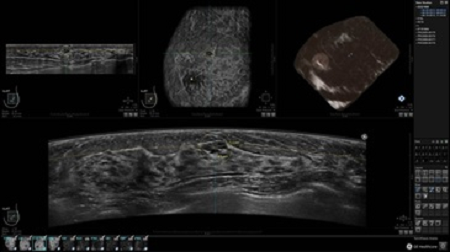

• Алгоритмы обработки изображений: алгоритм однородности изображения ткани (TEA), подавление зернистости, компенсация акустической тени от соска (NSC), определение границ молочной железы (BBD), определение стенки грудной клетки

• Встроенный сверхширокий вогнутый датчик C15-6XW: диапазон частот: 4 - 15 МГц; длина апертуры: 15,3 см; длина сканируемого участка: 16,9 см; количество элементов: 768

• Глубина сканирования до 5 см.

• Получение одного объемного изображения менее чем за 60 секунд

• Многорядная LED подсветка

• 64-битный преобразователь с широкими возможностями и инструментами для полноценного анализа и отчетности

• Изменяемая толщина среза: 0,5 - 10,0 мм (шаг 0,5 мм)

• Срез: 0,5 - 2,0 мм (шаг 0,5 мм)

• Инструмент увеличения 4X

• Просмотр кинопетель с регулируемой скоростью воспроизведения

• 360 ° APC - отображение области по «любой точке компаса»